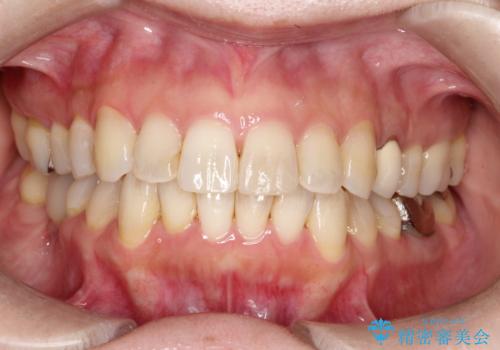

上下のがたつきをインビザラインで目立たない矯正

上顎の狭い歯列をインビザラインで拡大

上下前歯のデコボコをきれいに インビザラインによる矯正治療